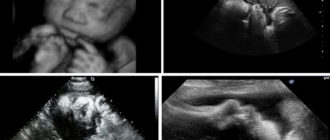

Как делают УЗИ на 38 неделе беременности: показания, подготовка, расшифровка На сроке 38 недель